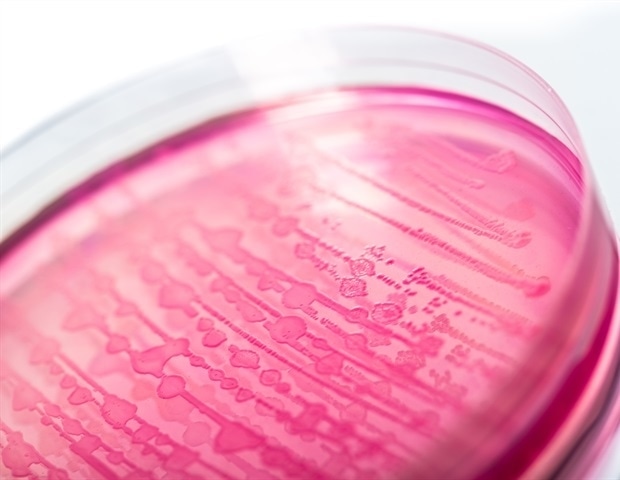

דרך מוזרות של אנטומיה, נשים נוטות במיוחד לדלקות בדרכי השתן, כאשר כמעט מחציתן מתמודדות עם אחת מהן בשלב מסוים בחייהן.